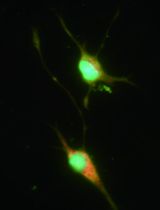

- Typically, more than 95% of live cells will be CD4+ T cells after four rounds of in vitro stimulation (Figure 3).

Figure 3. Representative FACS plots of a T cell line. Most living cells (> 95%) are CD4+ T cells (CD19- T cell receptor (TCR)β+CD90.2+CD4+ T cells) after 5 days of the fourth round of in vitro stimulation (Procedure E). Irradiated splenocytes can be seen as forward scatter (FSC)low, side scatter (SSC)low dead cells.